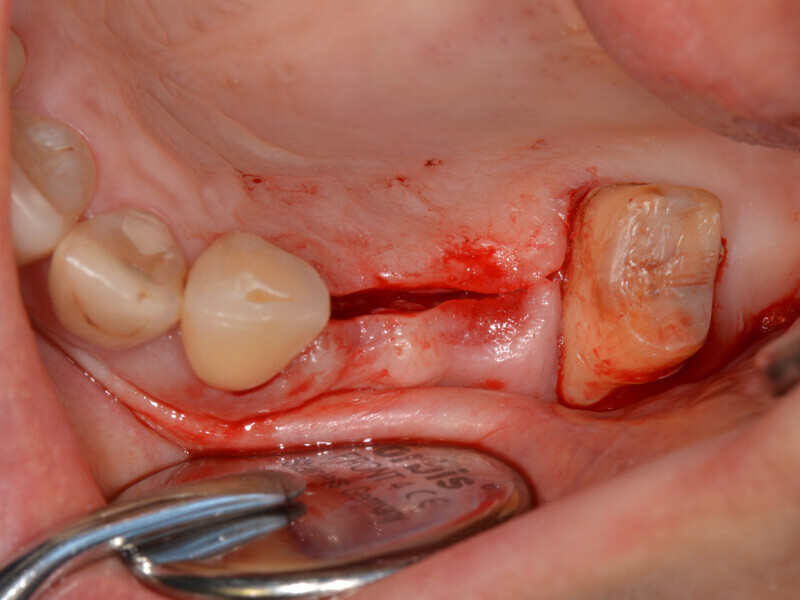

After local anaesthesia, a mid-crestal incision was performed and a mucoperiosteal flap was raised (Fig. 8). The flap design should be chosen such that the flap will not affect the positioning of the surgical guide. The osseous situation corresponded to the CBCT findings of a buccally atrophied alveolar ridge. After pilot drilling, the fully guided preparation was performed in accordance with the drilling protocol (Fig. 9). The vertical drilling up to just before the maxillary sinus was controlled by the surgical guide. The cortical bone of the sinus floor could then be selectively fractured using osteotomes and the Schneiderian membrane lifted to 11 mm, and subsequently bone substitute material was inserted (Bio-Oss, Geistlich; Fig. 10). After placement of the implants (Figs. 11 & 12), the buccal atrophy in regions #14 and 15 was reconstructed with bone substitute material and covered with a resorbable membrane (Bio-Gide, Geistlich; Fig. 13). Saliva-proof wound closure was performed using e-PTFE suture material.

Fig. 8: After the mid-crestal incision before raising the mucoperiosteal flap.